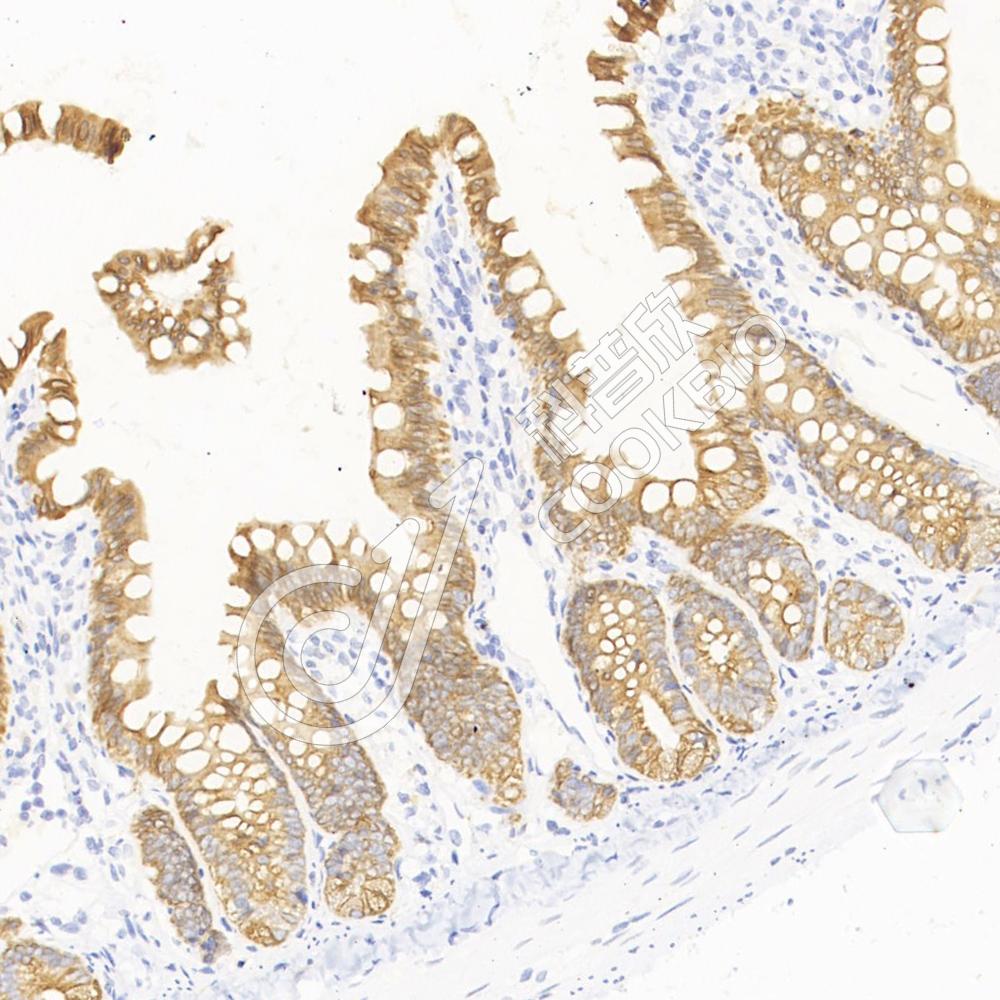

IHC检测Cytokeratin 5蛋白(货号 K1333738).

样品: 小鼠皮肤, 4%多聚甲醛 (货号KSG1101) 固定12-24小时.

抗原修复: 柠檬酸抗原修复液(干粉, pH 6.0) (KSG1201), 98℃, 20分钟.

—抗: 1: 2000稀释, 4℃ 孵育过夜.

二抗: S-vision免疫组化多聚二抗(山羊抗兔),即用型 (货号KB3906), 室温孵育20分钟.